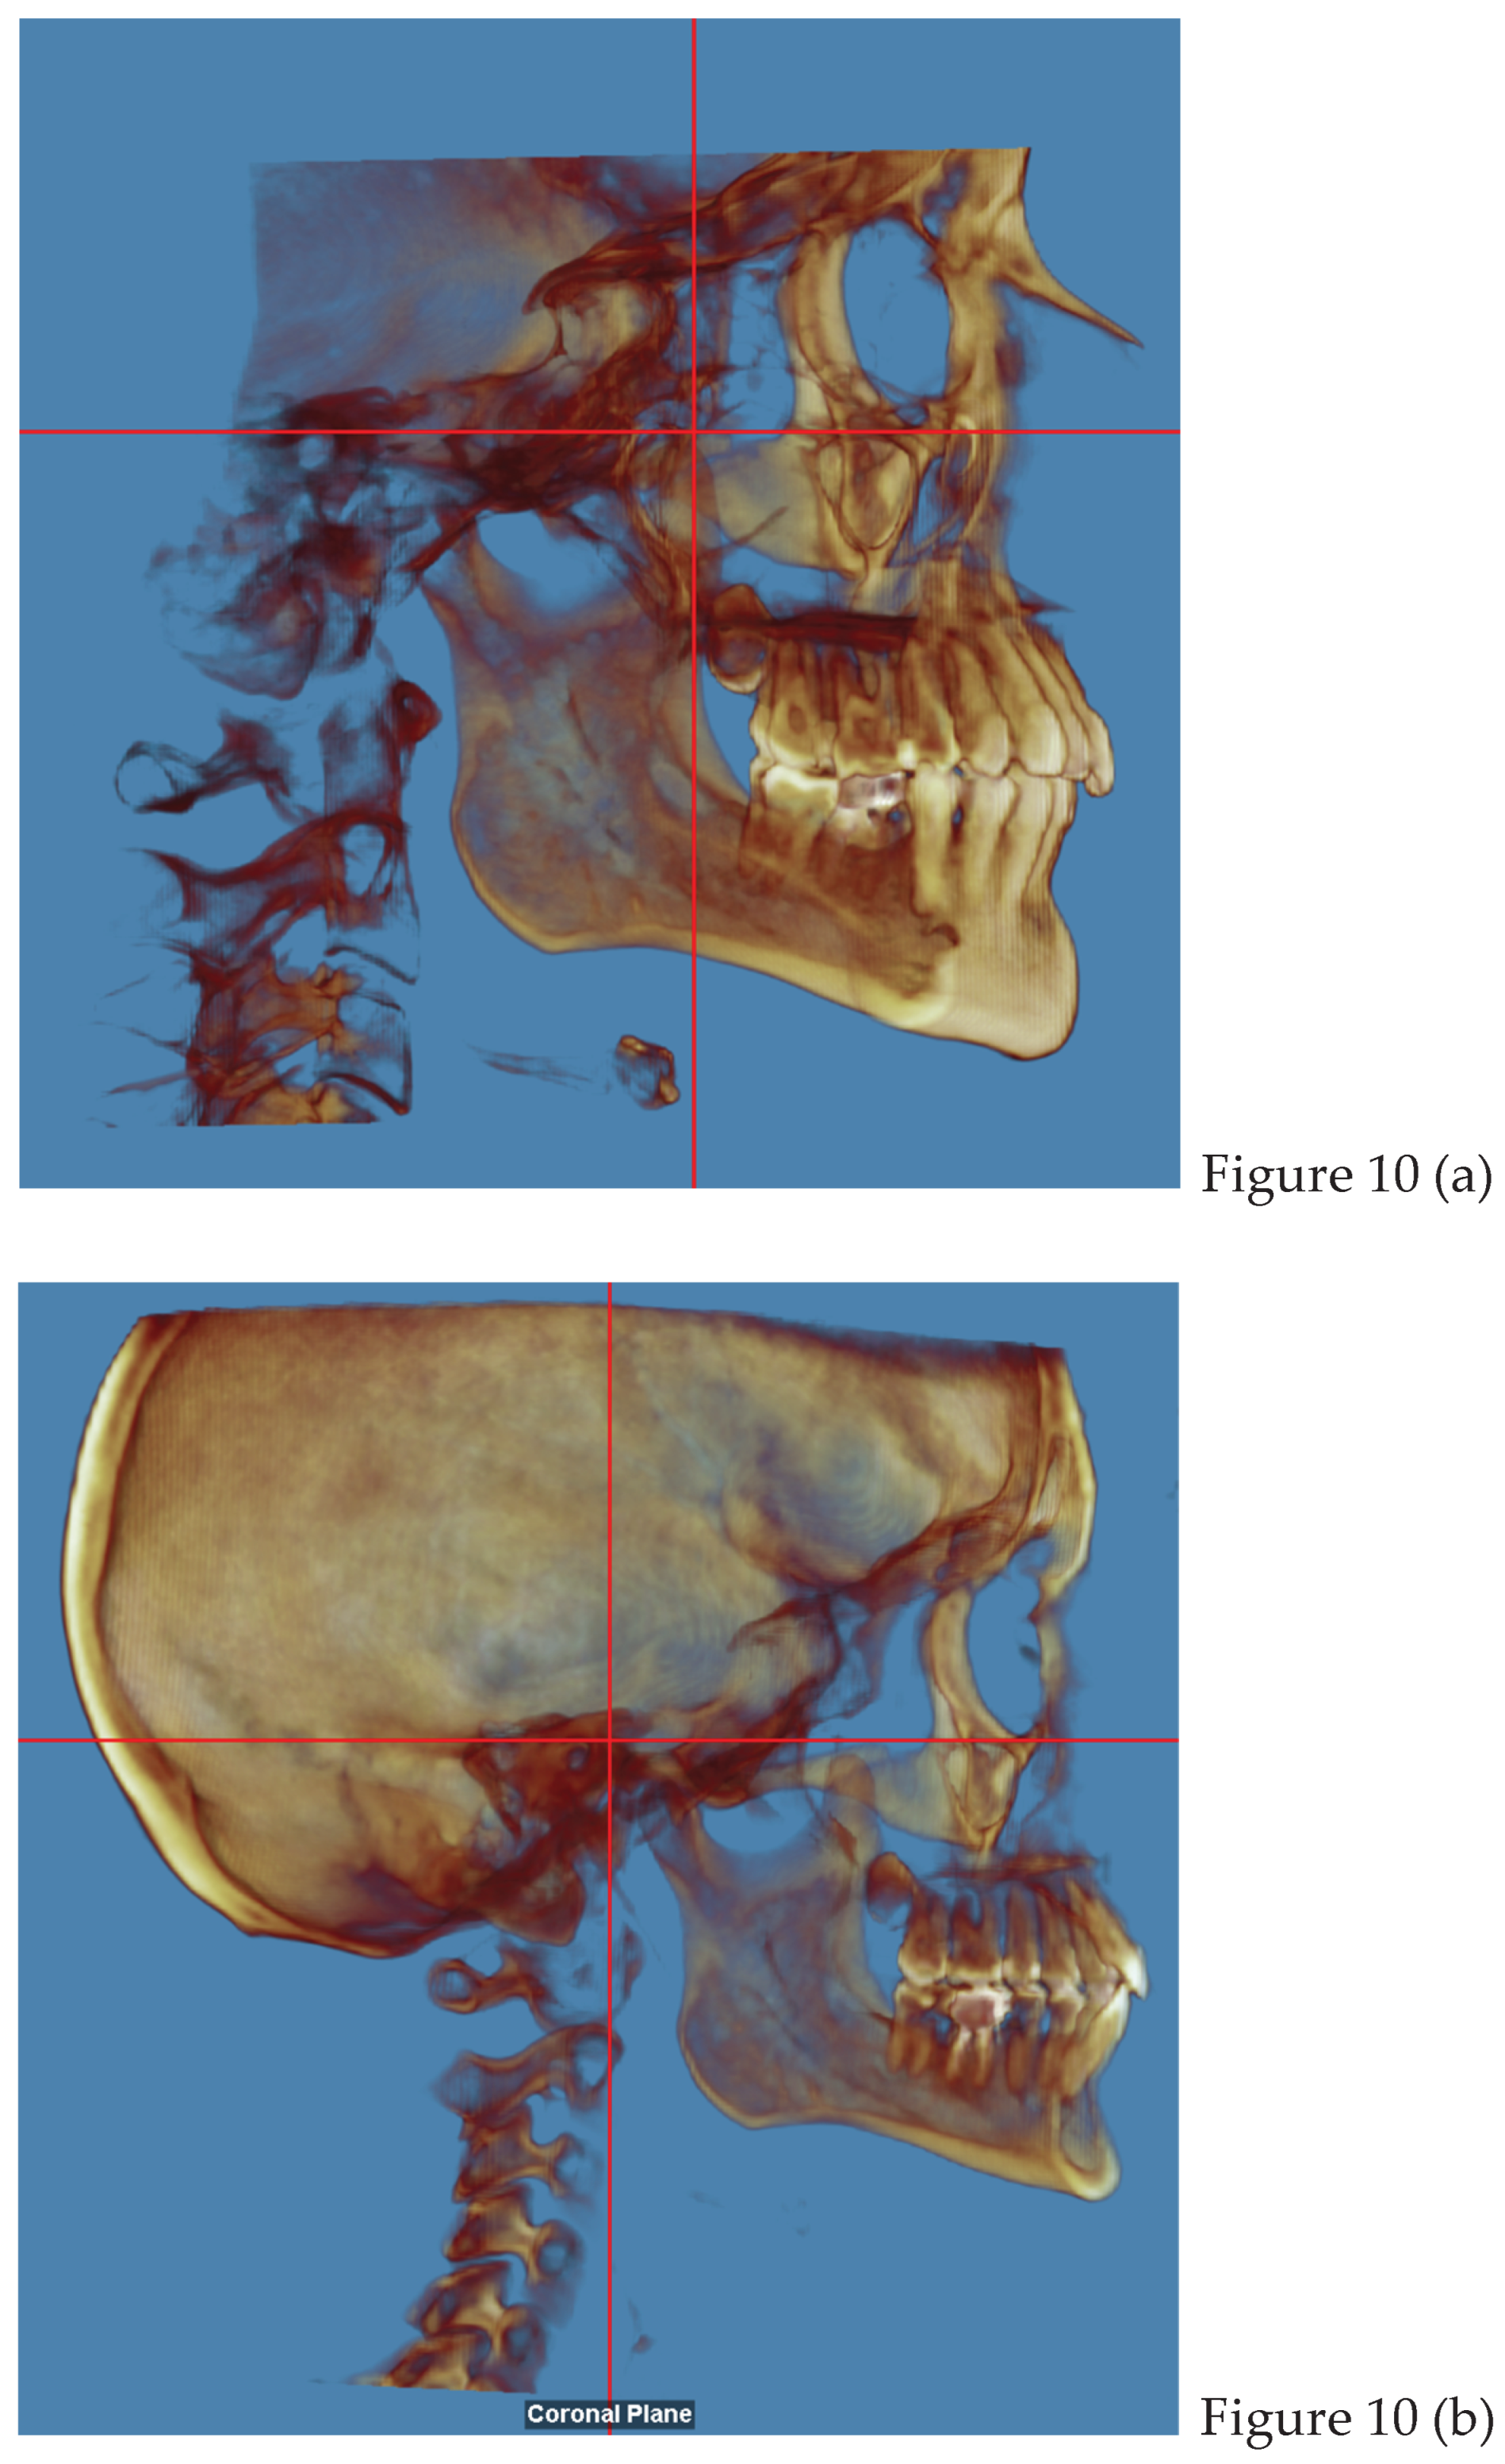

2.2. Cone Beam CT Analysis

- Sánchez CAF, Laverde COD, Rodríguez SEN, Gallego GAC, Aristizábal JF, Salazar OIC. Methodology for the correction of a CBCT volume from the skull to the natural head position. MethodsX. 2024 Nov 27;13:103073. [CrossRef] [PubMed] [PubMed Central]